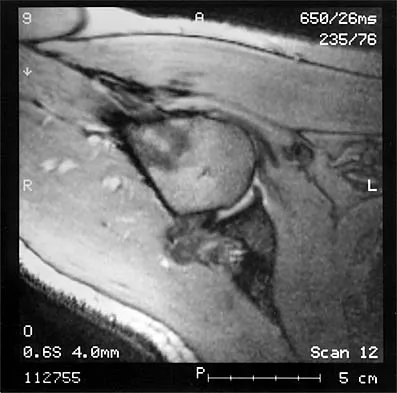

The MRI scan of the shoulder shown in Figure 2 was performed with the arm in abduction and external rotation. The image reveals what condition?